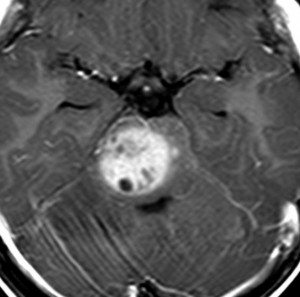

この脳幹部グリオーマは橋から小脳脚に浸潤したものです。びまん性橋膠腫の進行例にもみえますが,ガドリニウム増強のされ方が中心部で強すぎて非定型的です。これを生検術して病理確定診断をすれば,胎児性腫瘍やAP/RTという診断がつくのかもしれません。しかし,できることは局所放射線治療が主体の治療でなんらかの化学療法を組み合わせるくらいです。リスクの大きい病理診断で時を失うより早く治療を開始したほうがよいと思われる経過と画像でした。